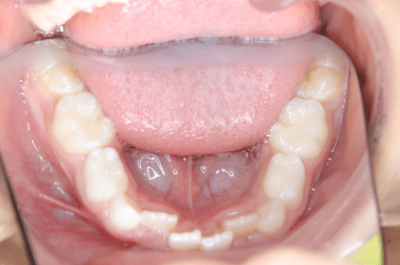

写真①:使用する装置例

写真①の装置を就寝時に使用することでこれらを改善していきます。